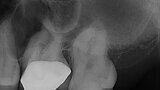

EdgeFile X7: Beastly bifurcation